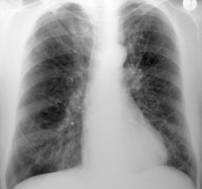

Emfizemul pulmonar cronic este forma cea mai frecvent intalnita si este consecinta obstructiei bronhiilor mici, cu distensia si atrofia peretilor bronhiolari, care are ca urmare destinderea alveolelor si cresterea volumului de aer alveolar. Aspectul radiologic este tipic. Cutia toracica are diametre marite, costele orizontalizate, spatiile intercostale largite, hemidiafragmele coborate si aplatizate, transparenta pulmonara este marita, spatiile retrosternal si retrocardiac marite, desenul pulmonar este mai accenuat, iar diafragmele cu miscarea inspiratorie mult redusa.

Fig. 28 Emfizemul pulmonar